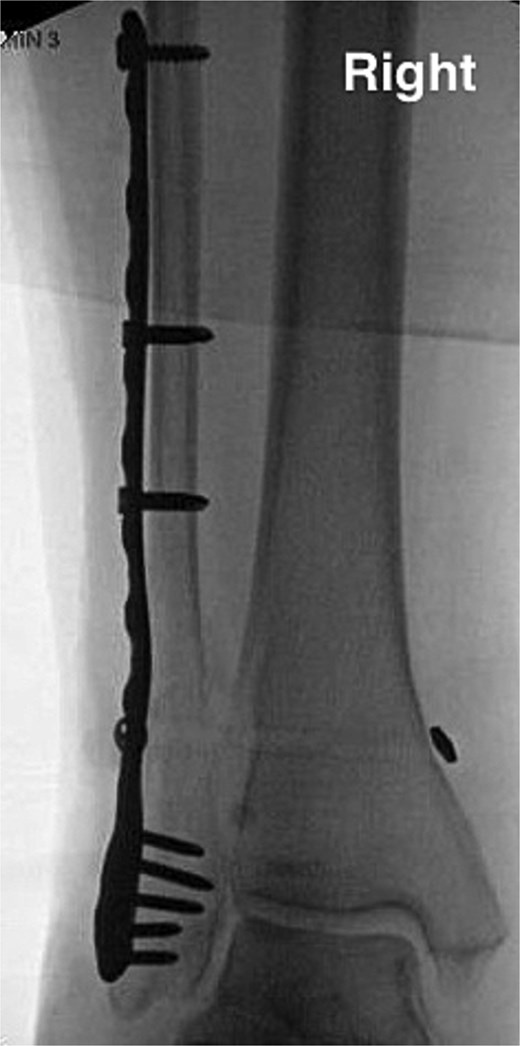

The patient is a 61-year-old female with a past medical history of idiopathic neuropathy with balance disorder, morbid obesity, and vitamin D deficiency presented to the clinic after she sustained an atraumatic injury to the right ankle. Notably, the patient required surgical treatment 2 years prior for an atraumatic left Weber C lateral malleolus fracture with Stage 3 posterior tibialis tendonitis and pes planus deformity (Fig. 1). Radiographs obtained at the time of injury to her right ankle showed no acute osseous abnormalities or dislocations and she was given a tall controlled ankle motion (CAM) boot. Magnetic resonance imaging (MRI) was later obtained demonstrating an acute Weber C fibular fracture with partial-thickness tearing of the syndesmotic membrane (Fig. 2). She was diagnosed with a right ankle lateral malleolus Weber C stress fracture. Patient initially elected for nonsurgical treatment but after a week with stable pain with limited function, she elected for surgical intervention a week after injury.

Anterior–posterior post-operative X-ray demonstrating fixation of left Weber C fibular fracture.